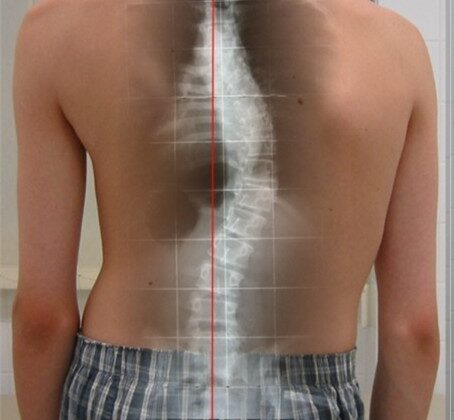

ما هو العمر الأكثر خطورة للإصابة باعوجاج العمود الفقري؟ سؤال يشغل بال الكثير من الأهل، خاصة عندما يلاحظون تغيرًا في شكل ظهر أو كتف طفلهم. اعوجاج العمود الفقري أو الجنف هو حالة طبية تتميز بانحناء غير طبيعي للعمود الفقري، وقد تظهر في أي عمر، لكن هناك مراحل عمرية يُعتبر ظهور المرض فيها أكثر خطورة من غيرها. في هذا المقال، سنوضح بشكل مبسط متى يظهر الجنف عادةً، ومن هم الأكثر عرضة، ولماذا تختلف خطورته بين الأطفال والبالغين.

تشخيص الجنف في مراحله المبكرة ليس أمرًا سهلاً. في البداية، قد لا يظهر الانحناء بوضوح، خاصة إذا كان بسيطًا. غالبًا يتم اكتشاف الحالة عندما يزداد الانحناء ليؤثر على شكل الجسم أو وضعية الأكتاف والحوض. ولهذا السبب قد تمر سنوات قبل أن يعرف الأهل أن طفلهم مصاب بالجنف.

كيف تكتشف اعوجاج العمود الفقري مبكرًا عند طفلك؟

من المهم أن يكون الأهل على وعي بالعلامات المبكرة، ومنها:

تفاوت في مستوى الأكتاف.

بروز أحد جانبي الصدر أكثر من الآخر.

ميل الجسم إلى أحد الجانبين.

عدم تساوي الخصر أو الوركين.

في حال ملاحظة أي من هذه العلامات، يجب استشارة الطبيب على الفور لعمل فحص سريري وتصوير بالأشعة إذا لزم الأمر.